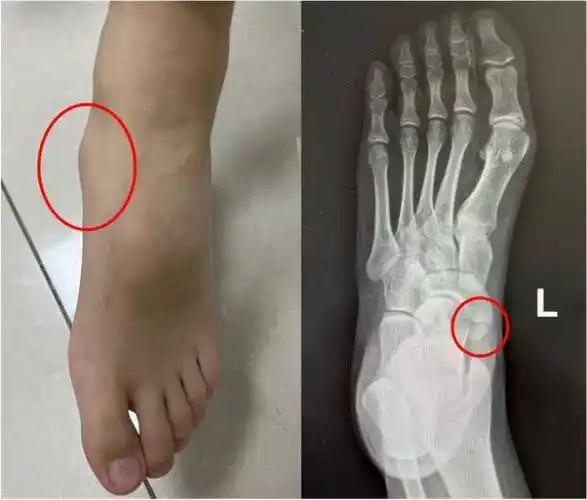

仁济健康丨孩子经常说脚痛!不是装怪 是多长了个骨头_症状_治疗_局部